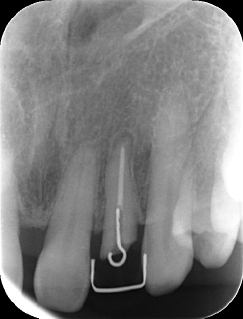

MTM開始直後と、終了後です。フックの位置が変わっているのがわかると思いますが、それが歯が動いた証拠となります。

歯からはフック、隣り合った歯にはワイヤーが渡してあります。そこにゴムをひっかけて歯を挺出させます。